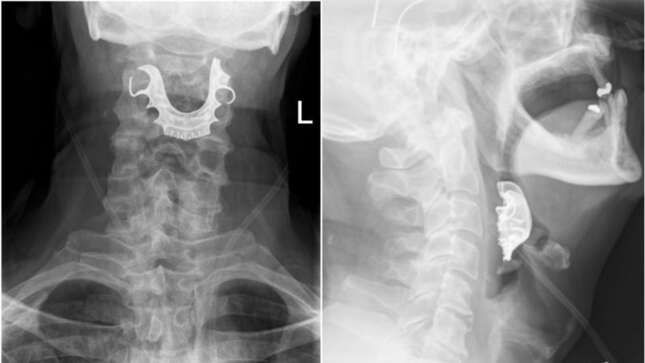

Pero cuando un nuevo grupo de médicos miró dentro de la garganta del hombre, después de que se quejase de sus síntomas, rápidamente detectaron que había algo alojado en su laringe. Y fue entonces cuando el hombre dijo que sus prótesis dentales habían desaparecido misteriosamente una semana antes.

Aunque los médicos pronto pudieron retirar la dentadura de la garganta con unas pinzas, el sufrimiento del hombre aún no había terminado.